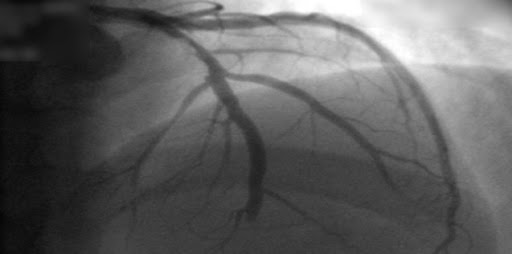

En pacientes con infarto de miocardio con elevación del segmento ST sometidos a revascularización percutánea completa, una estrategia guiada por la rserva fraccional de flujo no tuvo un beneficio significativo sobre una estrategia guiada por angiografía, si bien los intervalos de confianza para la estimación del efecto fueron amplios. New England Journal of Medicine, 22 de julio de 2021.